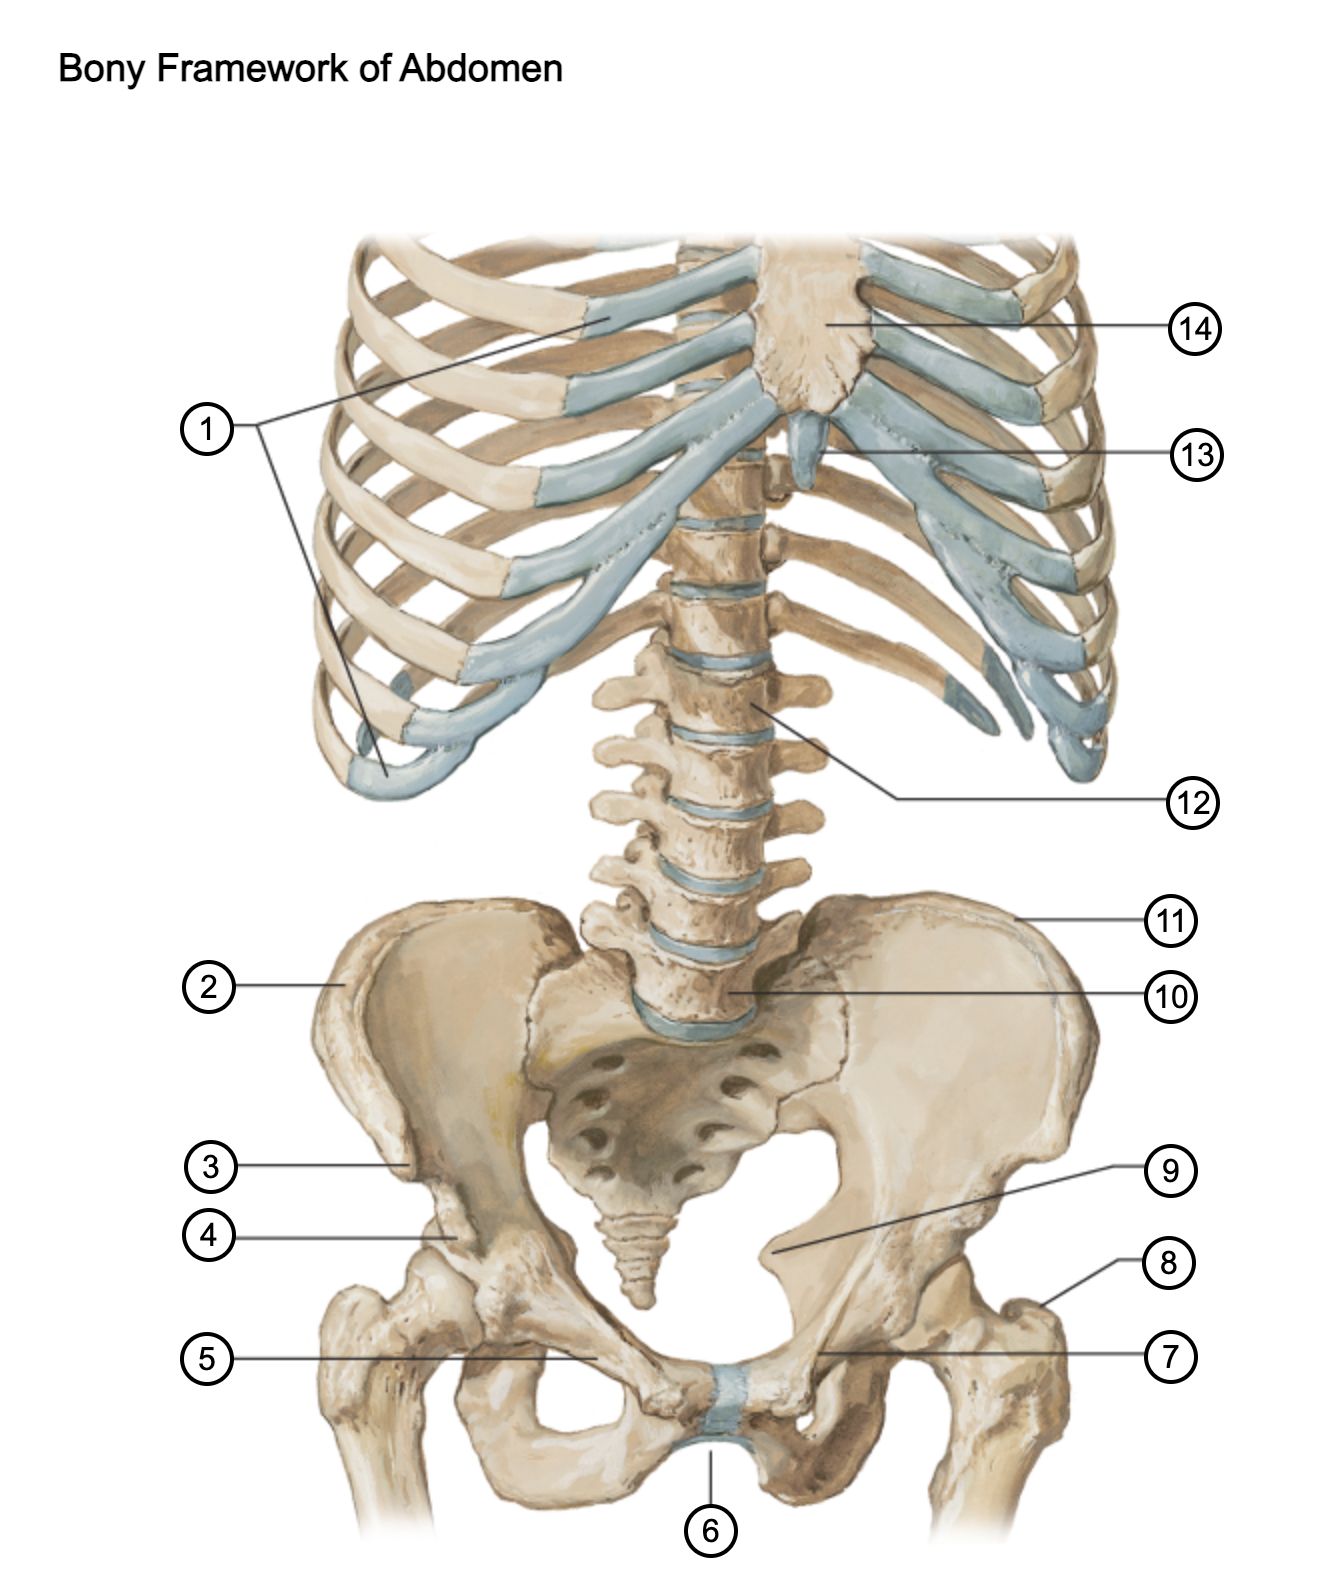

1

costal cartilages

2

iliac crest

3

anterior superior iliac spine

4

anterior inferior iliac spine

5

superior pubic ramus

6

pubic arch

7

pecten pubis

8

greater trochanter

9

ischial spine

10

L5 vertebra

11

iliac crest

12

L1 vertebra

13

xiphoid process

14

body of sternum